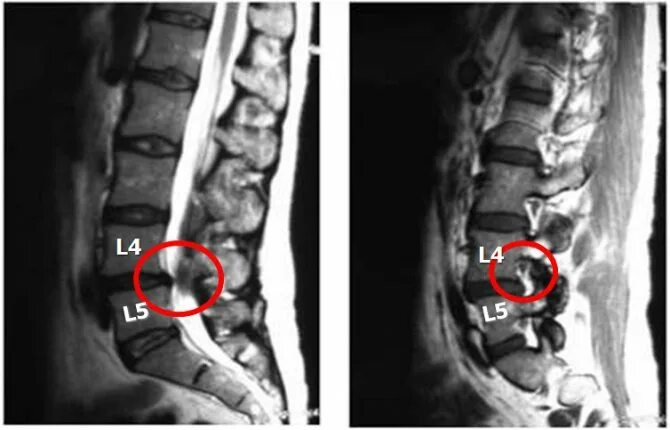

Протрузия дисков l3 4 5